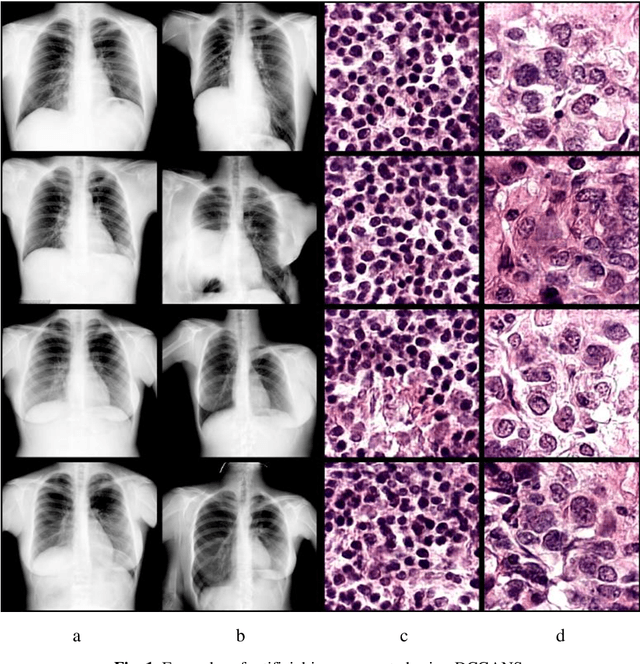

In this paper, we explore the possibility of generating artificial biomedical images that can be used as a substitute for real image datasets in applied machine learning tasks. We are focusing on generation of realistic chest X-ray images as well as on the lymph node histology images using the two recent GAN architectures including DCGAN and PGGAN. The possibility of the use of artificial images instead of real ones for training machine learning models was examined by benchmark classification tasks being solved using conventional and deep learning methods. In particular, a comparison was made by replacing real images with synthetic ones at the model training stage and comparing the prediction results with the ones obtained while training on the real image data. It was found that the drop of classification accuracy caused by such training data substitution ranged between 2.2% and 3.5% for deep learning models and between 5.5% and 13.25% for conventional methods such as LBP + Random Forests.